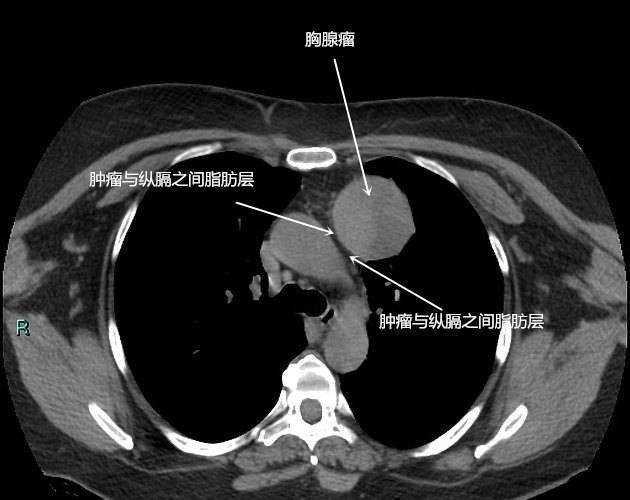

2.CT表现 良性胸腺瘤CT特点:(1)前纵隔内软组织密度圆形或卵圆形肿块;(2)肿块的周缘光滑锐利;(3)肿块的边缘有弧形钙化;(4)肿块的周围脂肪层存在完整;(5)临床症状不明显或无症状者。

胸腺癌CT特点:(1)胸腺肿块的周界不清,或具有分叶征象和毛刺征象;(2)胸腺肿块与附近的器官之间界限不清,其间的脂肪层(线)消失变形,为肿瘤组织代替;(3)胸腺肿块的密度(CT值)不均匀,可见坏死,出血和囊性变;(4)纵隔内组织器官受压变形,如上腔静脉受压变形、梗阻;(5)胸膜、心包增厚,出现胸腔、心包积液。